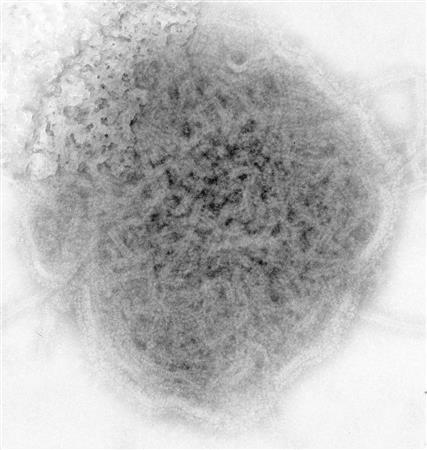

おたふくかぜの原因であるムンプスウイルスの電子顕微鏡画像(米疾病対策センター提供)